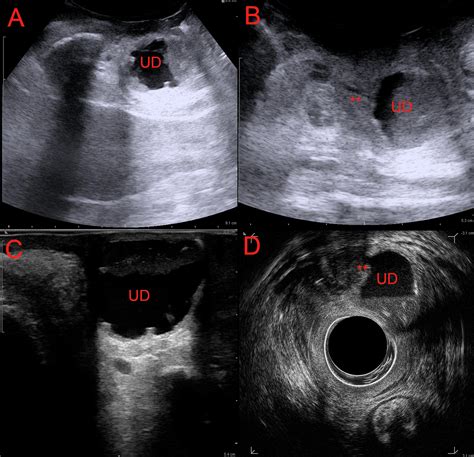

Diagnostic Procedures

Diagnosis requires a high index of suspicion, especially when standard treatments for UTIs fail. A physician will typically perform a physical exam, which may reveal a tender mass along the anterior vaginal wall. If pressure is applied to the mass, it is not uncommon for a small amount of urine or purulent discharge to exit the urethra.

MRI (Magnetic Resonance Imaging) The gold standard for visualizing the size and location of the diverticulum.

Voiding Cystourethrogram (VCUG) Uses contrast dye to see if the pouch fills during urination.

Urethroscopy Direct visualization of the urethra using a thin camera to locate the diverticular opening.